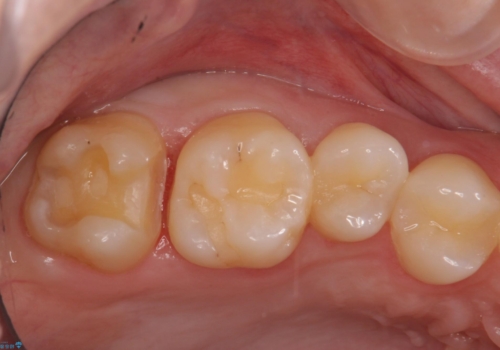

奥歯の虫歯治療でしたが、プラスチック周りと、歯と歯の間が大きな虫歯になっていました。

インレーでの修復予定でしたが、歯と歯の間が狭く、正確な型取りが難しい状態でした。

全体矯正をする前の虫歯チェックで見つかった虫歯です。